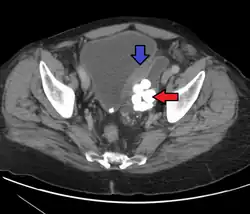

Transitional cell carcinoma

Transitional cell carcinoma is a type of cancer that arises from the transitional epithelium, a tissue lining the inner surface of these hollow organs.[1] It typically occurs in the urothelium of the urinary system; in that case, it is also called urothelial carcinoma. It is the most common type of bladder cancer and cancer of the ureter, urethra, and urachus. Symptoms of urothelial carcinoma in the bladder include hematuria (blood in the urine). Diagnosis includes urine analysis and imaging of the urinary tract (cystoscopy).